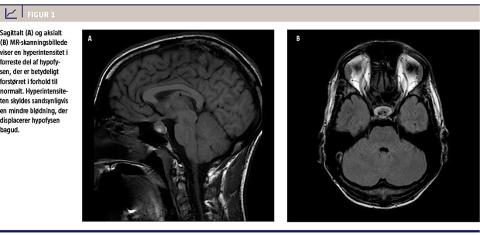

Somatisk og neurologisk undersøgelse ved indlæggelsen viste normale forhold. Hovedpinen viste sig at være refraktær for gængse analgetika. Blodprøvescreening, CT af cerebrum og lumbalpunktur inkl. undersøgelse for xantokromi viste ligeledes normale forhold. Patienten blev overflyttet til en neurologisk afdeling, hvor man ved MR-skanning af cerebrum påviste en mindre hyperintensitet i hypofysen (Figur 1) – denne tolkedes som fedtaflejring, evt. en mindre blødning eller infarcering. MR-angiografi viste normale intrakraniale kar. Efter én uges indlæggelse blev patienten udskrevet i habitualtilstand til kontrolskanning tre måneder senere.